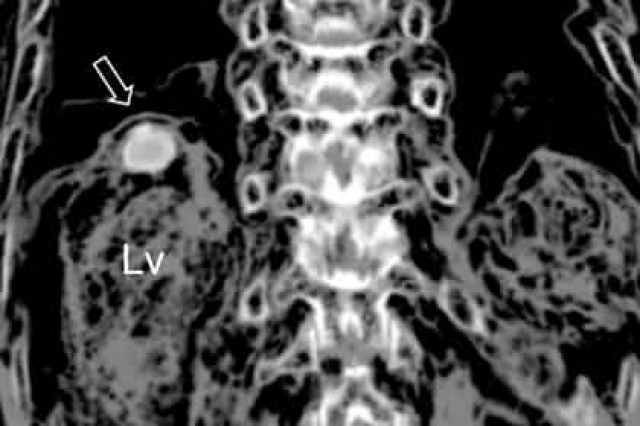

Мумия была найдена в 2014 году. Она принадлежала мужчине по имени Цзин Ли (Jing Lee), который умер в возрасте 63 лет и был похоронен на территории современного уезда Чхондо (расположен в южнокорейской провинции Кёнсан-Пукто). С разрешения потомков исследователи просканировали мумию с помощью компьютерной томографии. Оказалось, что в печени находятся золотисто-коричневые яйца легочного сосальщика длиной 85 микрометров.